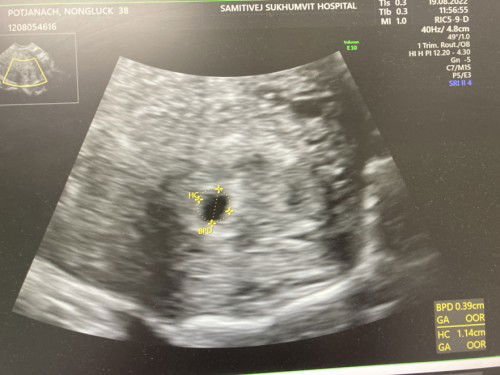

เลือดสีน้ำตาลออก อายุครรภ์ 5w4d

ท้อง 5w 4d. วันนี้มีเลือดสีน้ำตาลออก ไปอัลตราซาวด์ ยังไม่เจอตัวเด็กเลยค่ะ ขนาดถุงตั้งครรภ์ แค่0.39 cm ไม่รู้จะท้องลมหรือเปล่าค่ะ